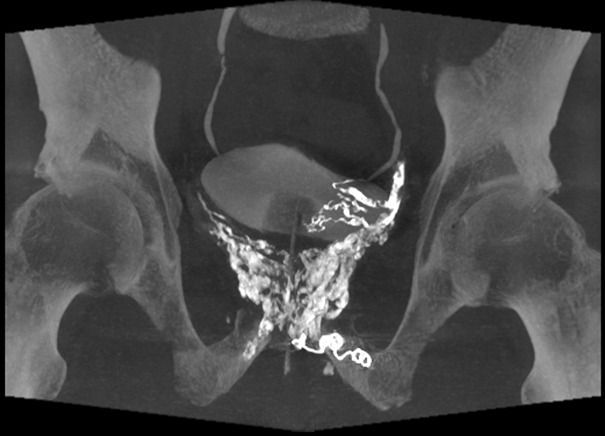

Au bilan scanographique, mise en évidence d’importantes varices pelviennes moulant la prostate !

Décision après concertation pluridisciplinaire de procéder à une phlébographie pelvienne. Celle-ci retrouve l’importantes varices pelviennes alimentées par les veines iliaques internes. Ces varices sont stagnantes et refluantes notamment vers le membre inférieur gauche (cf les coils sur l’image 1).